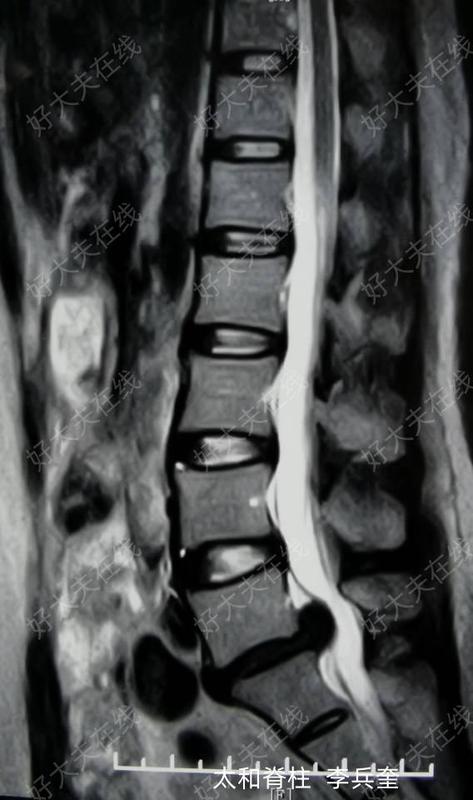

治療前患者因“腰痛伴左腿麻痛4年,加重1月”入院,近1月患者左腿疼痛麻木明顯,嚴重影響工作、生活及睡眠,下地活動困難,在外院行正規(guī)保守治療效果不佳,疼痛無緩解。腰椎MRI提示L5-S1巨大椎間盤突出(左旁中央型)。擬行微創(chuàng)脊柱內鏡下腰椎間盤突出髓核摘除術。治療后治療后2天患者恢復良好,左腿麻木疼痛消失,帶腰圍下地活動自如。手術切口0.8cm,美容縫合一針,無需拆線等特殊處理,擬今日出院。治療后0天手術順利,術中摘除L5-S1大量退變突出的椎間盤髓核組織。鏡下探查減壓徹底,神經根松弛。術后患者左腿痛即刻緩解,療效滿意。